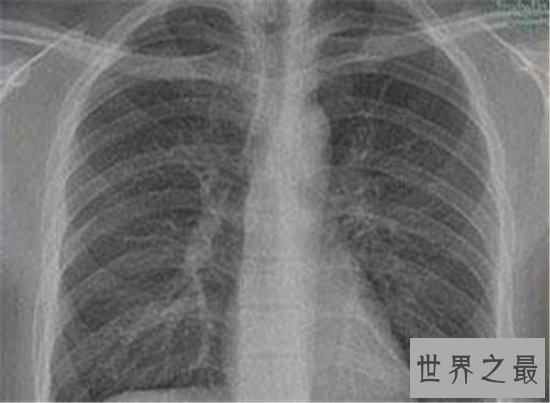

最长的英文单词,中文翻译过来名字是肺尘病。如果感兴趣的话可以去看看这个英语单词是什么样子的。而且这个单词一共有44个字母。我们平常普通生活中一个单词顶多也就十几个字母。这一个单词就直接顶了四个单词。

肺尘病其实是一种在我们生活中比较常见的疾病。主要原因就是因为吸入了大量的粉尘,对肺部造成了危害。经常咳嗽一类的。这类疾病其实非常严重,所以说如果万一有了这样的症状,一定要去看。千万不要耽误或不想去。